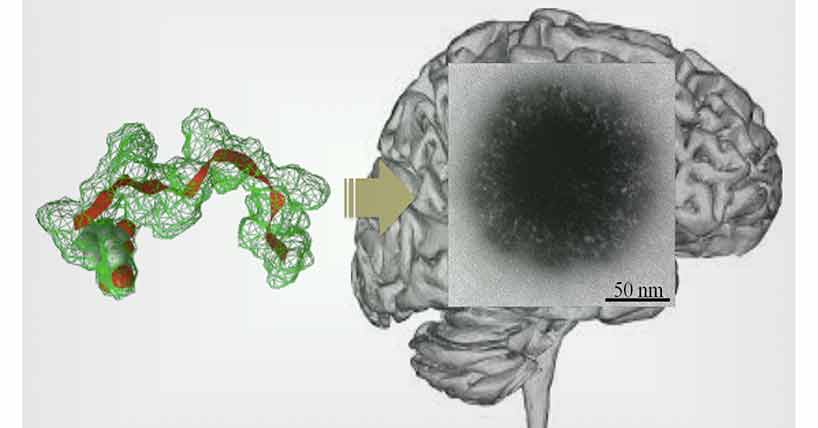

The team has now engineered small particles, similar to the size of viruses, from a peptide that can behave like a carrier to the brain and can be packed with drugs for intravenous injection.

The new technological breakthrough in delivering genetic materials to cells in the brain has used a peptide component from a virus that targets the brain (a bacteriophage fd). The peptide was synthesised and modified slightly, and when water was added it spontaneously formed a ‘small, hairy particle’.